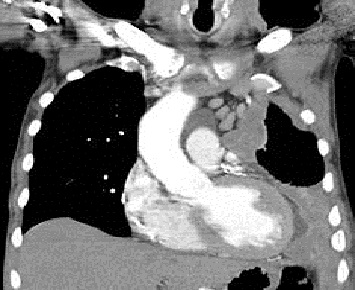

Mesothelioma (or, more precisely, malignant mesothelioma) is a rare form of cancer that develops from cells of the mesothelium, the protective lining that covers many of the internal organs of the body. Mesothelioma is most commonly caused by exposure to asbestos.1 The most common anatomical site for mesothelioma is the pleura (the outer lining of the lungs and internal chest wall), but it can also arise in the peritoneum (the lining of the abdominal cavity), the pericardium (the sac that surrounds the heart),2 or the tunica vaginalis (a sac that surrounds the testis).

Signs and symptoms of mesothelioma include shortness of breath due to pleural effusion (fluid between the lung and the chest wall), chest wall pain and constitutional signs such as unexplained weight loss. The diagnosis may be suspected based on chest X-ray and CT scan findings, but must be confirmed either by examining serous effusion cytology or with a biopsy (removing a sample of the suspicious tissue). A thoracoscopy (inserting a tube with a camera into the chest) can be used to acquire biopsy material, and allows the introduction of substances such as talc to obliterate the pleural space (a procedure called pleurodesis), preventing more fluid from accumulating and pressing on the lung. Despite treatment with chemotherapy, radiation therapy or sometimes surgery, mesothelioma carries a poor prognosis. Research about screening tests for the early detection of mesothelioma is ongoing.